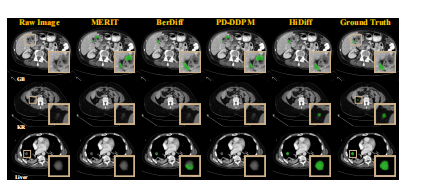

Fig. 8. Cross-dataset qualitative results of different segmentationmethods for four cases from the MSD testing set.

图 8. 不同分割方法在 MSD 测试集中四个案例的跨数据集定性结果。